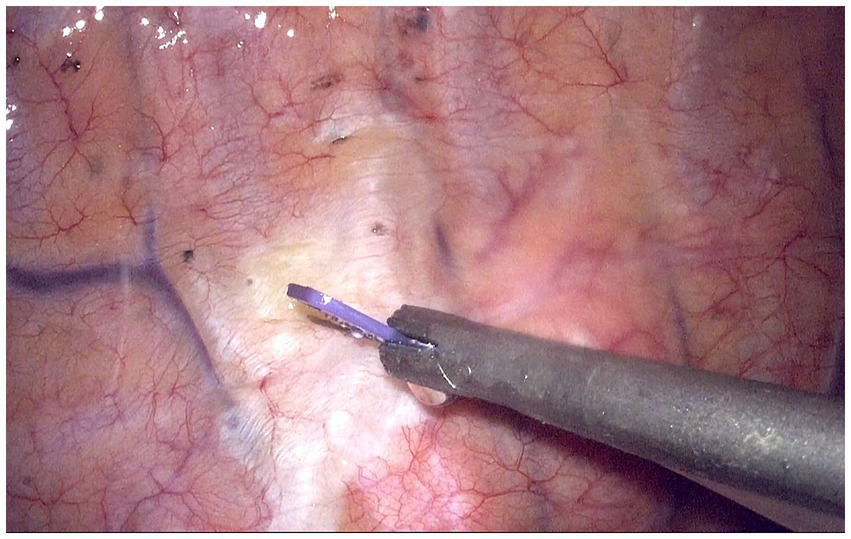

Both groups received 0.2 μg/kg sufentanil 30 min before the end of surgery. Furthermore, T group patients received TG-TPB before the chest was closed. Under thoracoscopic guidance, a 25G (0.5 mm) needle with an infusion tube was vertically inserted into the thoracic paravertebral space at the fourth intercostal plane and 0.2 cm lateral to the sympathetic chain. The puncture depth was ~0.5 cm below the parietal pleura. Subsequently, 20 mL 0.375% ropivacaine was injected (Figure 2). Conversely, P group patients received TG-TPB with 20 mL 0.9% NaCl.

Figure 2

Thoracoscopic guided thoracic paravertebral block at fourth intercostal levels. The white raised area indicates the diffusion of local anesthetics in the paravertebral space.